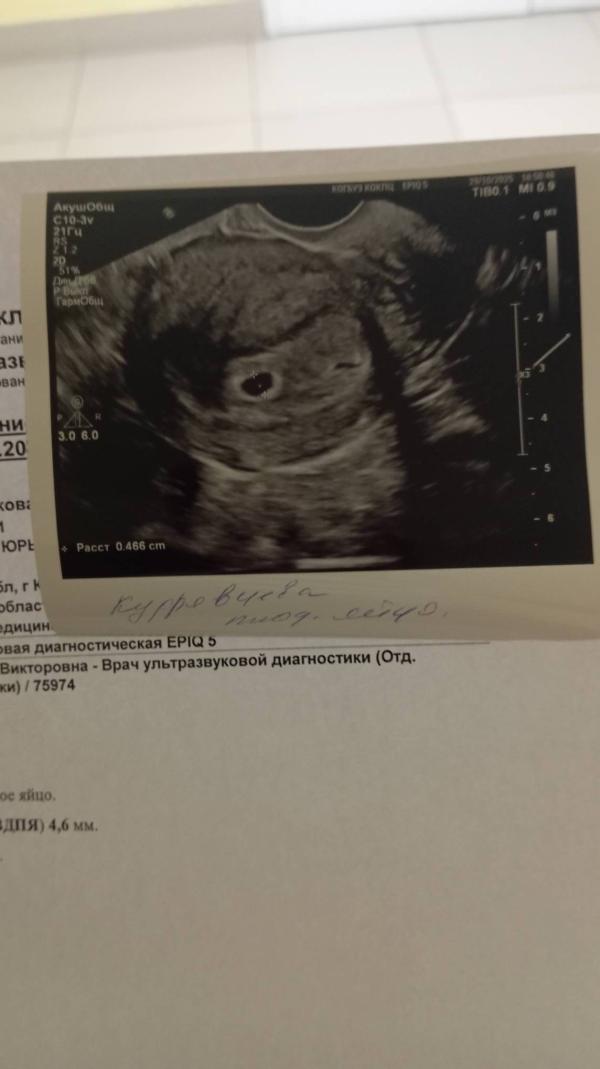

Бусинка внутри) подросли немного)

@saikabalalaika555 на первом УЗИ ничего не было тоже,на второе пя было 2,4 мм